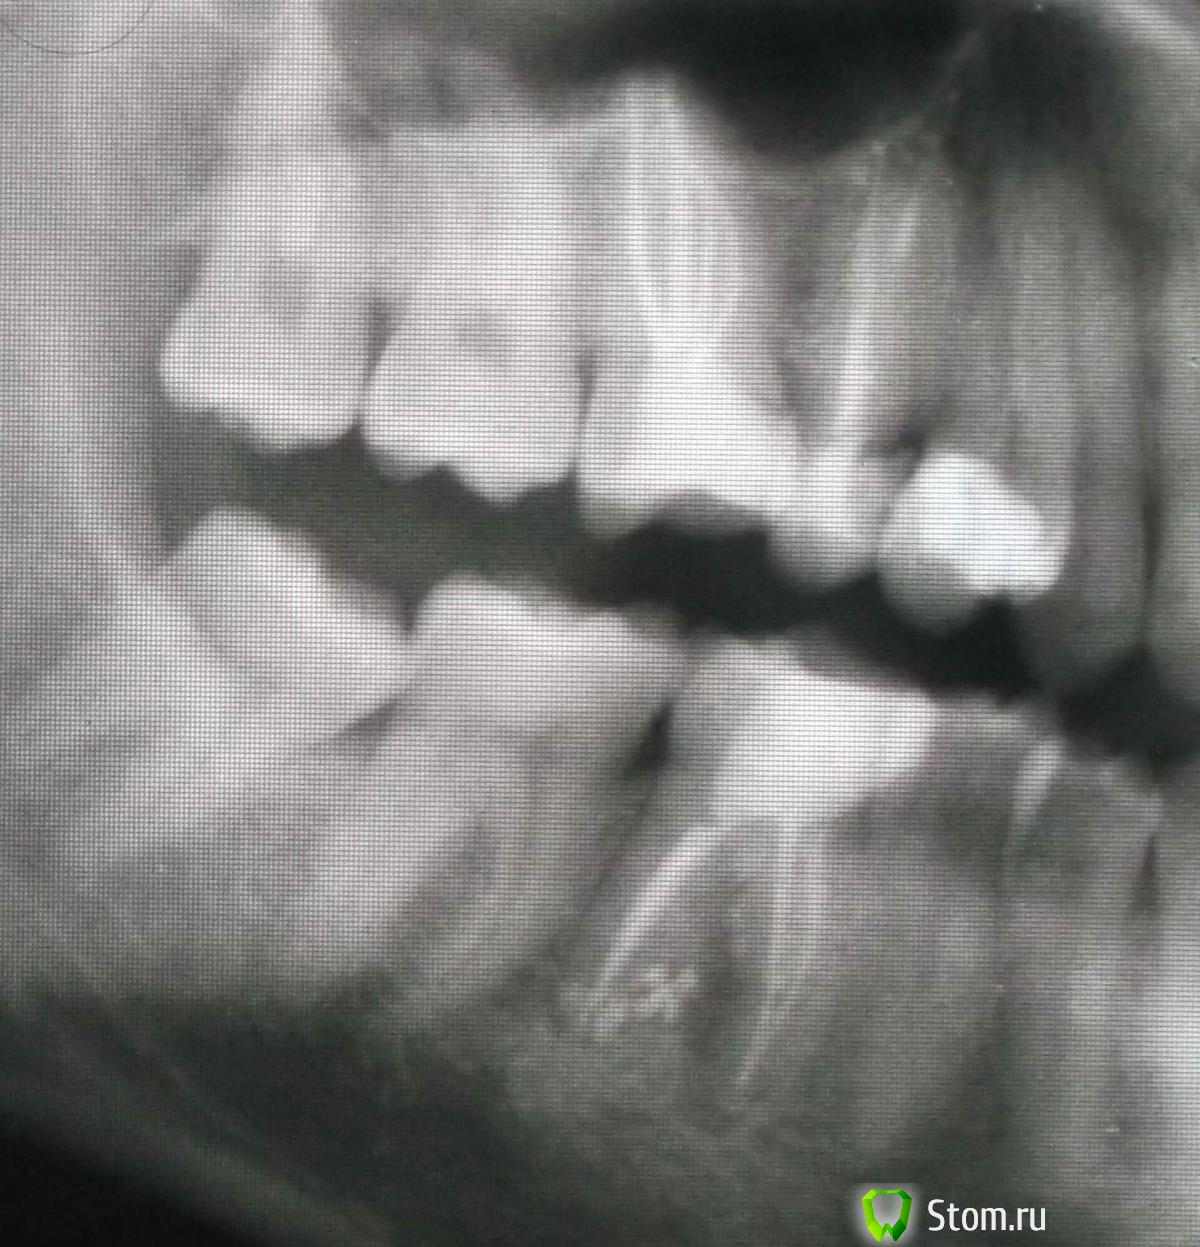

FBR Опубликовано 31 марта, 2012 Поделиться Опубликовано 31 марта, 2012 Удаление штифта. Восстановление культевой вкладкой. Металлокерамическая коронка. И обратите внимание на 16 зуб - его надо перелечивать, т.к. на медиальном корне- гранулема (воспаление). Ссылка на комментарий

FBR Опубликовано 31 марта, 2012 Поделиться Опубликовано 31 марта, 2012 (изменено) Удаление штифта. Восстановление культевой вкладкой. Металлокерамическая коронка. И обратите внимание на 16 зуб - его надо перелечивать, т.к. на медиальном корне- гранулема (воспаление).Пардон - на 46 зуб Изменено 31 марта, 2012 пользователем FBR Ссылка на комментарий